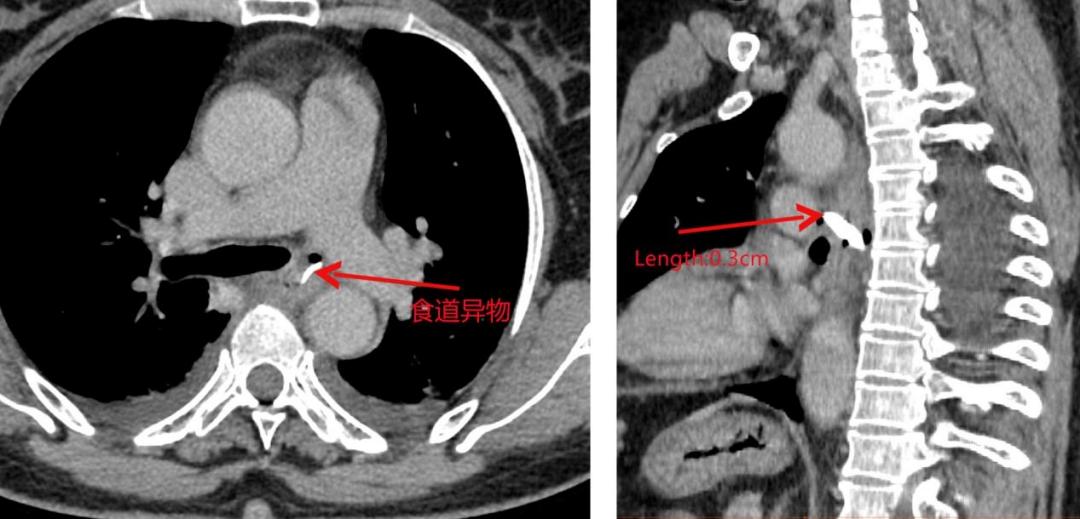

近日,一名59岁女性患者因进食鸡骨后导致吞咽困难到宣汉县人民医院就诊,检查发现食管异物已穿出食管前后壁,异物前端距左肺动脉3mm。

因患者病情危重,手术难度大,宣汉县人民医院胸心外科专业、消化内镜中心、手术麻醉科团队等多学科进行联合会诊后认为,单纯胸腔镜取出异物或单纯胃镜取出异物风险较大,有造成二次损伤和左肺动脉及降主动脉损伤的可能,决定采取胸腔镜联合电子胃镜取出异物的手术方案。在多学科通力协作下,医务人员通过胸腔镜下分离和保护好左肺动脉及降主动脉在胃镜下成功为该名患者取出食管异物。